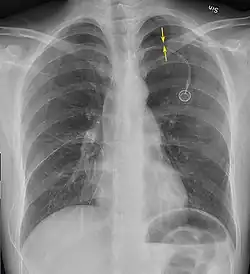

Chest X-ray

A plain chest radiograph, ideally with the X-ray beams being projected from the back (posteroanterior, or "PA"), and during maximal inspiration (holding one's breath), is the most appropriate first investigation.[35] It is not believed that routinely taking images during expiration would confer any benefit.[36] Still, they may be useful in the detection of a pneumothorax when clinical suspicion is high but yet an inspiratory radiograph appears normal.[37] Also, if the PA X-ray does not show a pneumothorax but there is a strong suspicion of one, lateral X-rays (with beams projecting from the side) may be performed, but this is not routine practice.[18][22]

It is not unusual for the mediastinum (the structure between the lungs that contains the heart, great blood vessels, and large airways) to be shifted away from the affected lung due to the pressure differences. This is not equivalent to a tension pneumothorax, which is determined mainly by the constellation of symptoms, hypoxia, and shock.[16]

The size of the pneumothorax (i.e. the volume of air in the pleural space) can be determined with a reasonable degree of accuracy by measuring the distance between the chest wall and the lung. This is relevant to treatment, as smaller pneumothoraces may be managed differently. An air rim of 2 cm means that the pneumothorax occupies about 50% of the hemithorax.[18] British professional guidelines have traditionally stated that the measurement should be performed at the level of the hilum (where blood vessels and airways enter the lung) with 2 cm as the cutoff,[18] while American guidelines state that the measurement should be done at the apex (top) of the lung with 3 cm differentiating between a "small" and a "large" pneumothorax.[38] The latter method may overestimate the size of a pneumothorax if it is located mainly at the apex, which is a common occurrence.[18] The various methods correlate poorly but are the best easily available ways of estimating pneumothorax size.[18][22] CT scanning (see below) can provide a more accurate determination of the size of the pneumothorax, but its routine use in this setting is not recommended.[38]

Not all pneumothoraces are uniform; some only form a pocket of air in a particular place in the chest.[18] Small amounts of fluid may be noted on the chest X-ray (hydropneumothorax); this may be blood (hemopneumothorax).[16] In some cases, the only significant abnormality may be the "deep sulcus sign", in which the normally small space between the chest wall and the diaphragm appears enlarged due to the abnormal presence of fluid.[19]